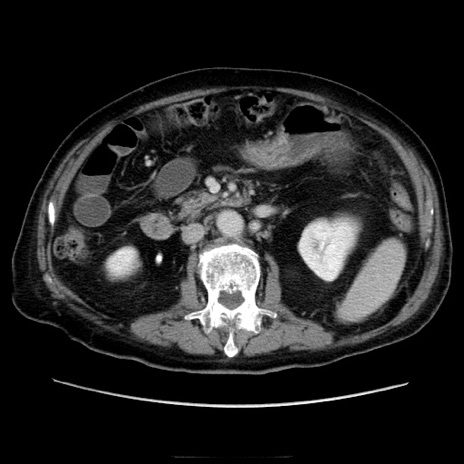

症例21(横断像)

【症例】70歳代男性

【主訴】腹痛

【現病歴】肝硬変・肝細胞癌にてかかりつけの方。約9時間前に食後より腹痛出現。症状が徐々に増悪し、嘔吐出現したため来院。

【既往歴】肝硬変、肝細胞癌(RFA、TACE後)

【身体所見】意識清明、表情苦悶様、BT 36℃、BP 129/78mmHg、P 88bpm、SpO2 97%(RA)、右上腹部から心窩部にかけて圧痛あり、反跳痛なし、筋性防御あり。

【データ】WBC 5800、CRP 0.16